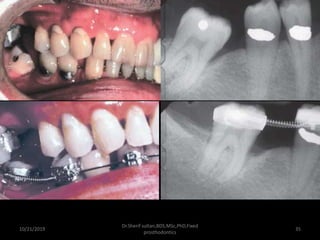

• #28 Surgical crown lengthening. A, Fractured and carious second premolar. B, Reflection of a flap and removal of granulation tissue. C, Bone removed on the mesial aspect to increase the distance to the fracture site to 3.5 mm. D, Distally, the bone is removed so that there will be 3.5 mm from the caries to the alveolar crest. E, Healing after the surgical crown lengthening. F, Definitive crown restoration after cementation, before restoration of the sextant with a removable dental prosthesis